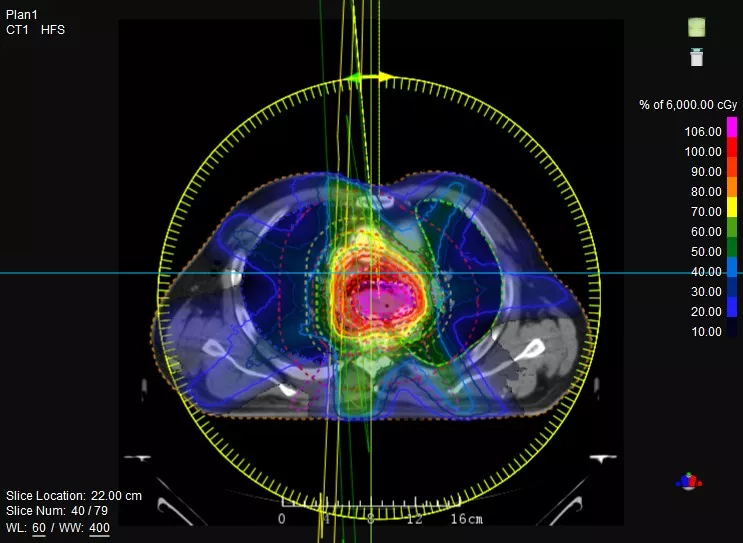

一款設(shè)備即可滿足CT模擬定位、CT影像引導(dǎo)、uARC動態(tài)旋轉(zhuǎn)調(diào)強放療等重要臨床應(yīng)用,無需科室/治療室間切換,一站完成放療全流程。

機(jī)載CT影像可直接用于放療計劃制作

鼻咽癌患者,進(jìn)行旋轉(zhuǎn)容積調(diào)強治療(uARC)